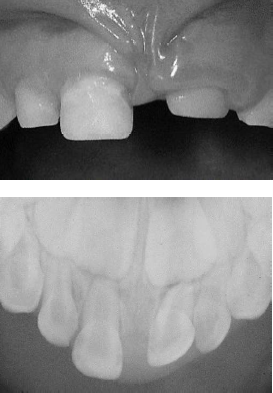

Com base nas imagens apresentadas e considerando os aspectos clínico e radiográfico de uma criança de 4 anos de idade, 20 dias após luxação intrusiva completa, julgue os itens a seguir.

A técnica radiográfica de escolha para traumatismos em dentes decíduos anteriores é a tomada oclusal modificada com o filme periapical adulto, podendo haver complementação com a tomada lateral com filme periapical adulto ou oclusal em caso de luxação intrusiva.